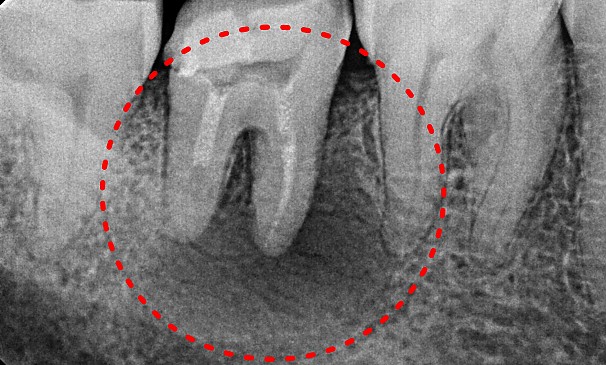

치아살리기 치료

자연치아를 최대한 살려

오래 쓸 수 있도록 최선을 다합니다.

자연치아를 최대한 살려

오래 쓸 수 있도록 최선을 다합니다.

치아살리기 치료